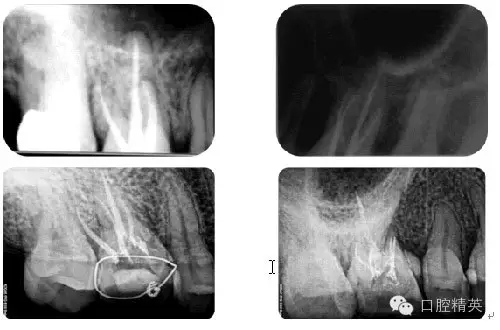

根管治療病例觀賞

病例1:常規(guī)根管治療

病例2:各型MB2根管

病例3:C型根管

病例4:根管再治療

病例5:遺漏根管再治療

病例6:折斷器械取出

病例7:根尖切除術(shù)